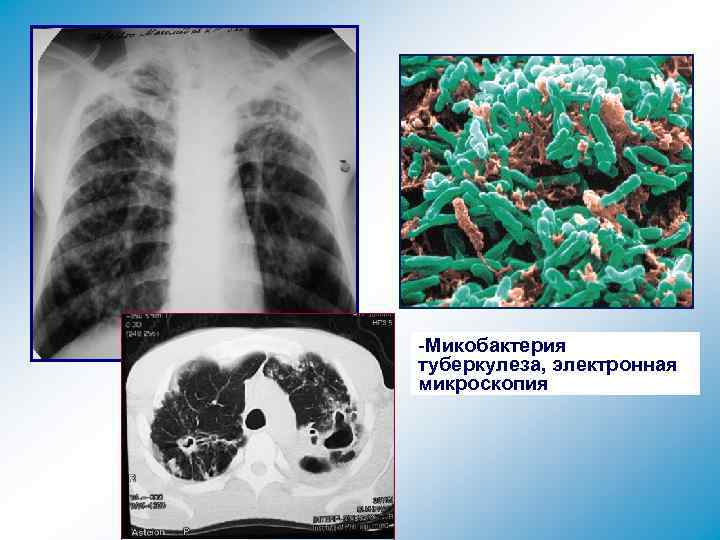

-Микобактерия туберкулеза, электронная микроскопия